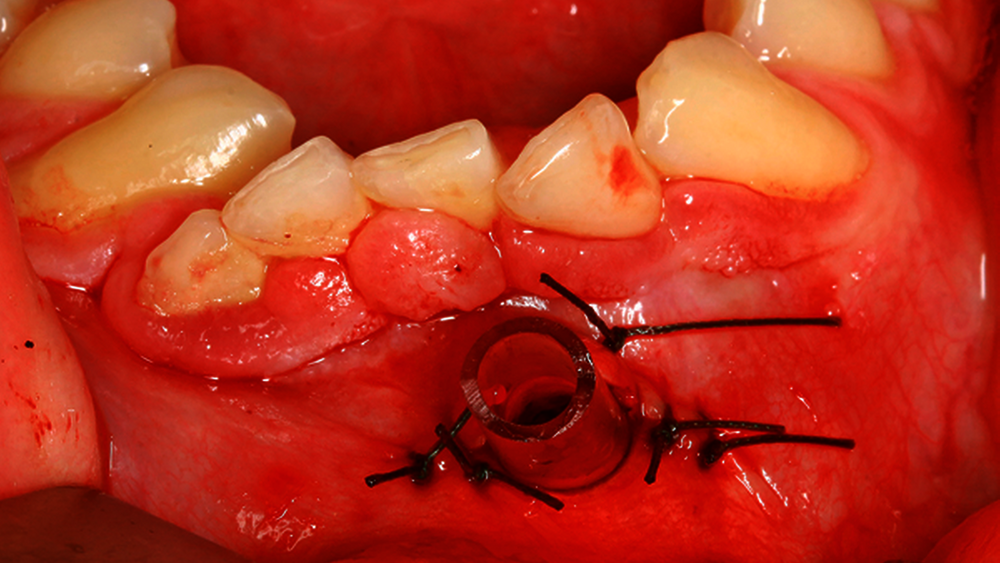

Nach Darstellung der Zyste beziehungsweise des Zystenbalgs erfolgt die Gewinnung einer repräsentativen Probe. Hiernach erfolgen die Spülung des Zystenlumens und das Absaugen des Inhalts. Anschließend wird ein Drainageröhrchen eingebracht und nach Readaptation des Mukoperiostlappens mittels Naht fixiert (Abbildung 1).